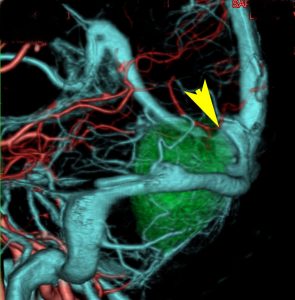

若い女性に偶然発見されたものです。直静脈洞と静脈洞交会の接合部あたりに発生したもので,静脈洞はほぼ閉塞に近い所見でした。しかし,この部分の静脈洞は,テント硬静脈側副路が発達することがあるので,硬膜を含めた積極的な摘出をすることは絶対にできません。もしほんの少しでも流れがある直静脈洞を閉塞させると短時間に脳死になるような脳静脈圧亢進が生じる可能性があるからです。静脈洞内に少し取り残して(右下の矢印)手術を終了しました。手術後には定位放射線治療を行って再増大を防ぎます,